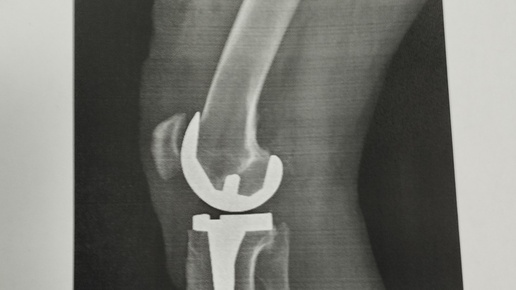

Эндопротезирование коленного сустава

Друзья, неделю назад заменил коленный сустав на правой ноге. И, хочу поделиться этой информацией - может быть кому-то будет интересно или поможет тем, кто собирается на такую операцию. Не обещаю быстро и развёрнуто отвечать на вопросы -пишу с телефона и не часто имею возможность такую. Сразу скажу- дело происходит в Москве. Знаю, что, к сожалению по мнению многих Москва и Россия разные государства (((, но слышал от друзей, что и в других регионах, например в Сибири, сейчас уже дела с такими операциями очень неплохие...